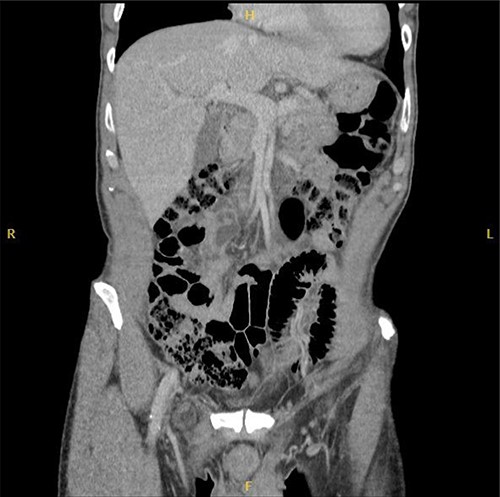

Computed tomography (CT) was reported as demonstrating an inguinal hernia containing fat and possibly the vermiform appendix (Figs 1 and 2). There was no conclusive evidence of appendicitis.